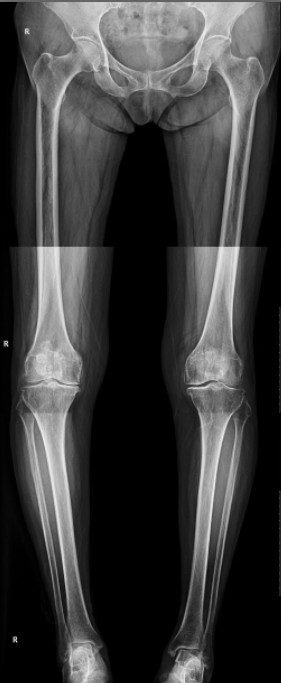

病例二:患者女性,82歲。主因“右膝疼痛10年伴加重、活動(dòng)受限半個(gè)月”入院。入院前右膝痛時(shí)好時(shí)壞,疼痛劇烈時(shí)無法站立。

患者術(shù)前全長

患者術(shù)后

患者術(shù)后全長